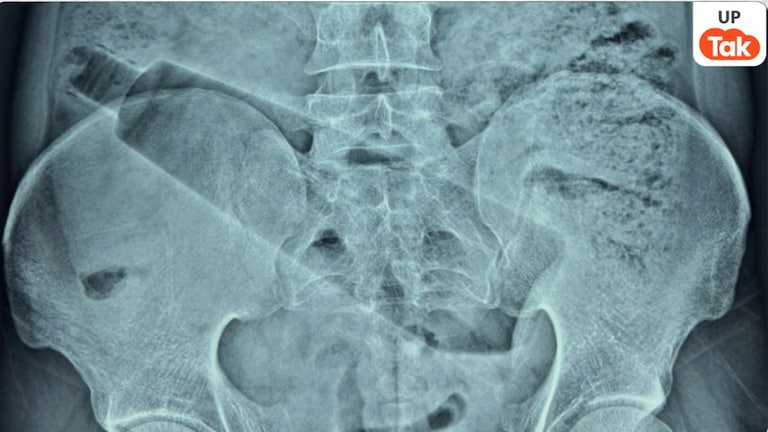

UP News: उत्तर प्रदेश के अम्बेडकर नगर जिले से एक हैरान कर देने वाला मामला सामने आया है. यहां का एक युवक गुजरात के अहमदाबाद में काम करता था. करीब 7 दिन पहले वह नशे में था. तभी उसने अपने मलाशय में प्लास्टिक की बोतल डाल ली. ये बोतल उसके पेट तक पहुंच गई. इसके बाद से उसके पेट में दर्द रहने लगा और ये दर्द लगातार बढ़ता गया.